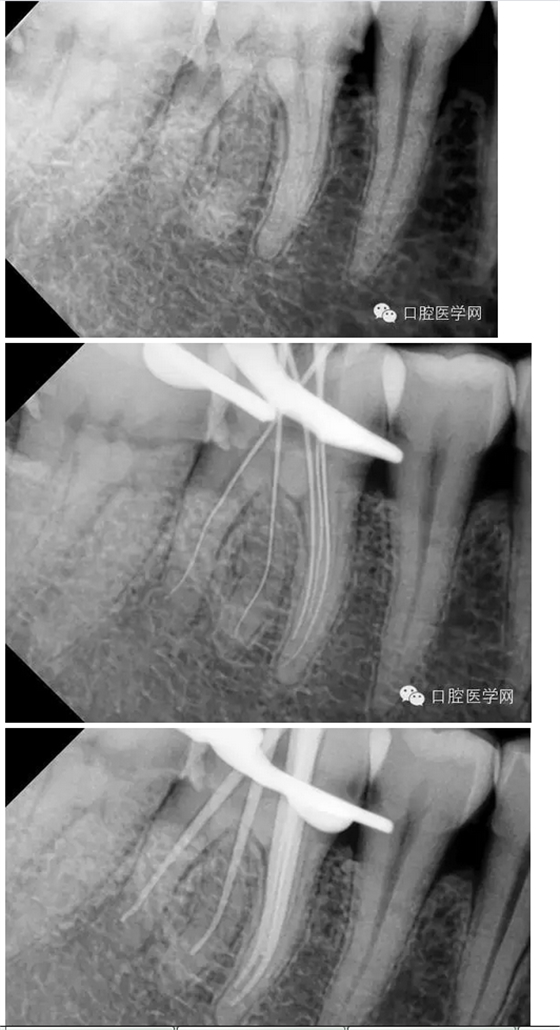

患者:男,44歲

主訴:右下后牙進(jìn)食痛2周,加重2天。

現(xiàn)病史:牙齒有洞,無不適,未處理,2周前開始進(jìn)食痛,口服消炎藥,好轉(zhuǎn),2天前晚上劇烈疼痛,今來看診。

檢查:#46牙頰側(cè)小洞,探(++),叩(-),冷熱(+++),咬頜正常,牙齦未見不適,未見其它不適。

診斷:#46牙髓炎

治療計(jì)劃:#46根管治療+冠修復(fù)保護(hù)。